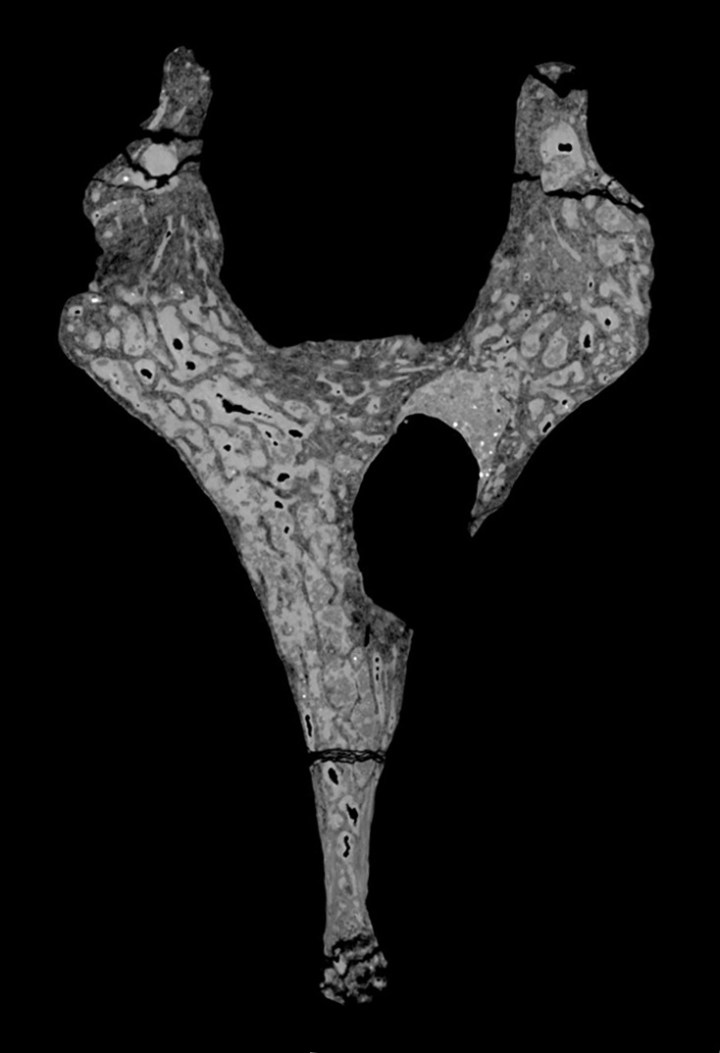

Nel secondo studio, un team di scienziati ha identificato il più antico tumore benigno mai scoperto nei fossili umani nella vertebra di un giovane Australopithecus sediba, noto come Karabo. Si trovava nel sito di Malapa, a pochi chilometri da Swartkrans, ed è stato datato a 1,98 milioni di anni fa. Finora, il più antico possibile tumore in un hominine era stato scoperto in Croazia nella costola di un Neanderthal datato a circa 120.000 anni fa.

Il tumore dell’australopiteco

L’autore capo dello studio sul tumore, Patrick Randolph-Quinney, suggerisce: «La presenza di un tumore benigno nell’Australopithecus sediba è affascinante non solo perché è stato trovato nella schiena, un posto estremamente raro per una tale malattia negli uomini moderni, ma anche perché si tratta di un ragazzino (di 12-13 anni, ndr). In effetti è la prima prova di questa malattia in un giovane individuo nell’intera documentazione fossile umana».

Il professore Lee Berger, autore di entrambi gli studi e a capo del progetto Malapa (il sito del ritrovamento delle vertebre dell’Australopithecus sediba), ha aggiunto: «Non solo si supponeva che questi tipi di cancro e di tumore fossero malattie della modernità, cosa che questi fossili smentiscono chiaramente, ma si credeva che tali malattie fossero la conseguenza di una vita più lunga, mentre questo raro tumore è stato trovato in un ragazzino. La storia di questi tipi di tumori e cancri è molto più complessa di quanto pensassimo».